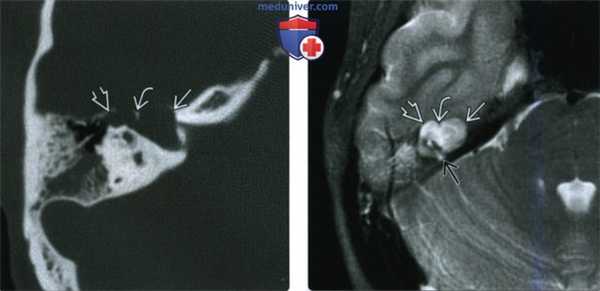

Рис. 1. КТ пациента с холестеатомой левой височной кости — деструкция костной стенки внутренней сонной артерии (маленькая стрелка), базального и среднего завитков улитки, задней грани пирамиды (большая стрелка).

Рис. 2. Выделены сигмовидный синус (большая стрелка), срединная пластинка черепной ямки (изогнутая стрелка), холестеатома (пунктирная стрелка), канал лицевого нерва (маленькая стрелка).